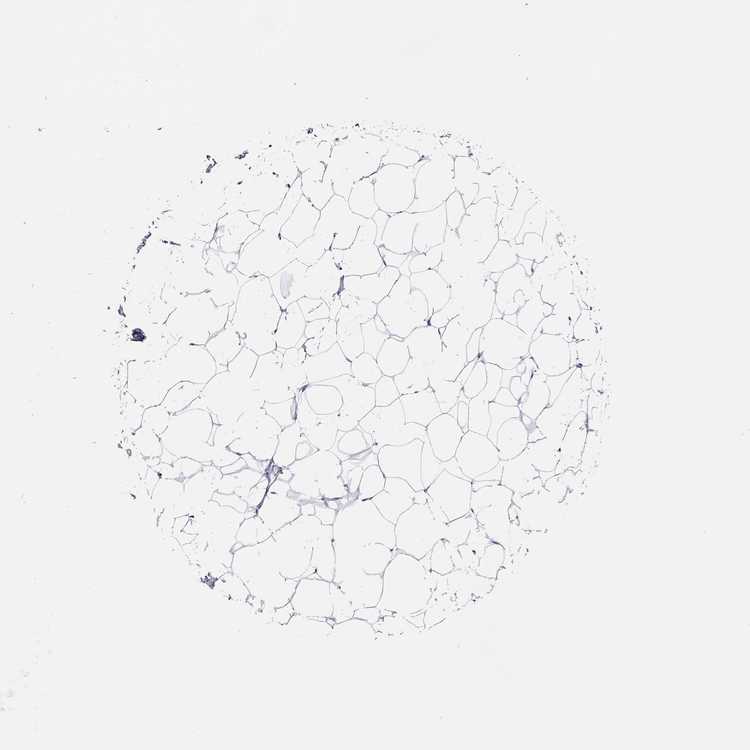

BREAST - Antibody stainingi

Antibody staining in the annotated cell types in the current human tissue is reported as not detected, low, medium, or high, based on conventional immunohistochemistry profiling in selected tissues. This score is based on the combination of the staining intensity and fraction of stained cells.

Each image is clickable and will lead to virtual microscopy that enables deeper exploration of all samples and also displays staining intensity scores, fraction scores and subcellular localization as well as patient and tissue information for each sample.

Antibody HPA072129

Adipocytes Not detected

Glandular cells Not detected

Myoepithelial cells Not detected